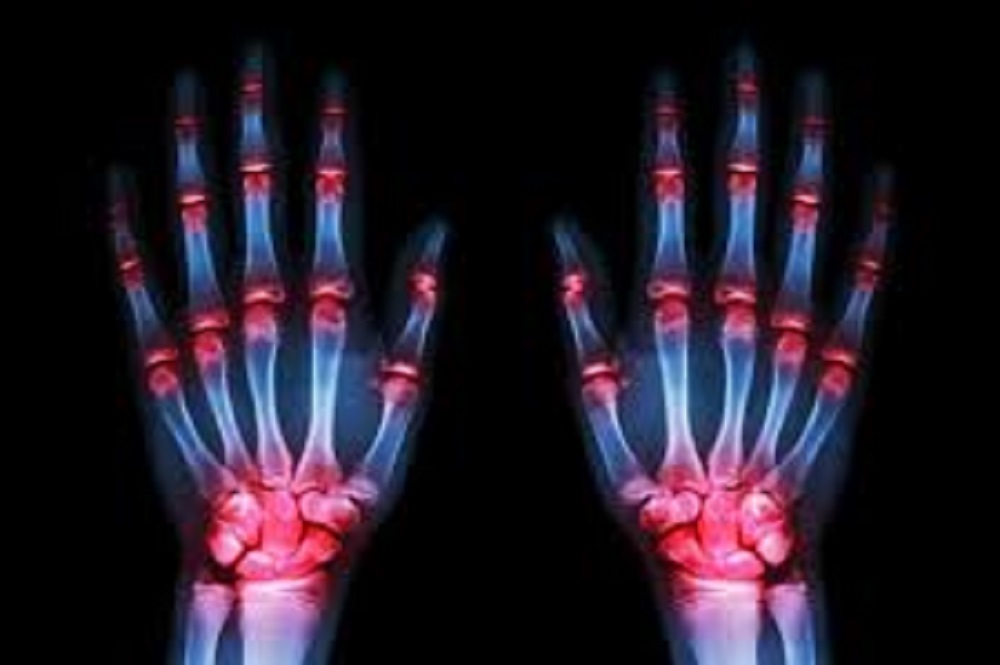

Approximately 1.5 million individuals in the U.S. suffer from rheumatoid arthritis. | File photo

The Arthritis Foundation states that approximately 1.5 million individuals in the U.S. suffer from RA and that women are 2 to 3 times more likely to experience RA symptoms than men are. While RA can affect individuals beginning in their 30s to 60s, most individuals do not experience noticeable symptoms until their 60s.'